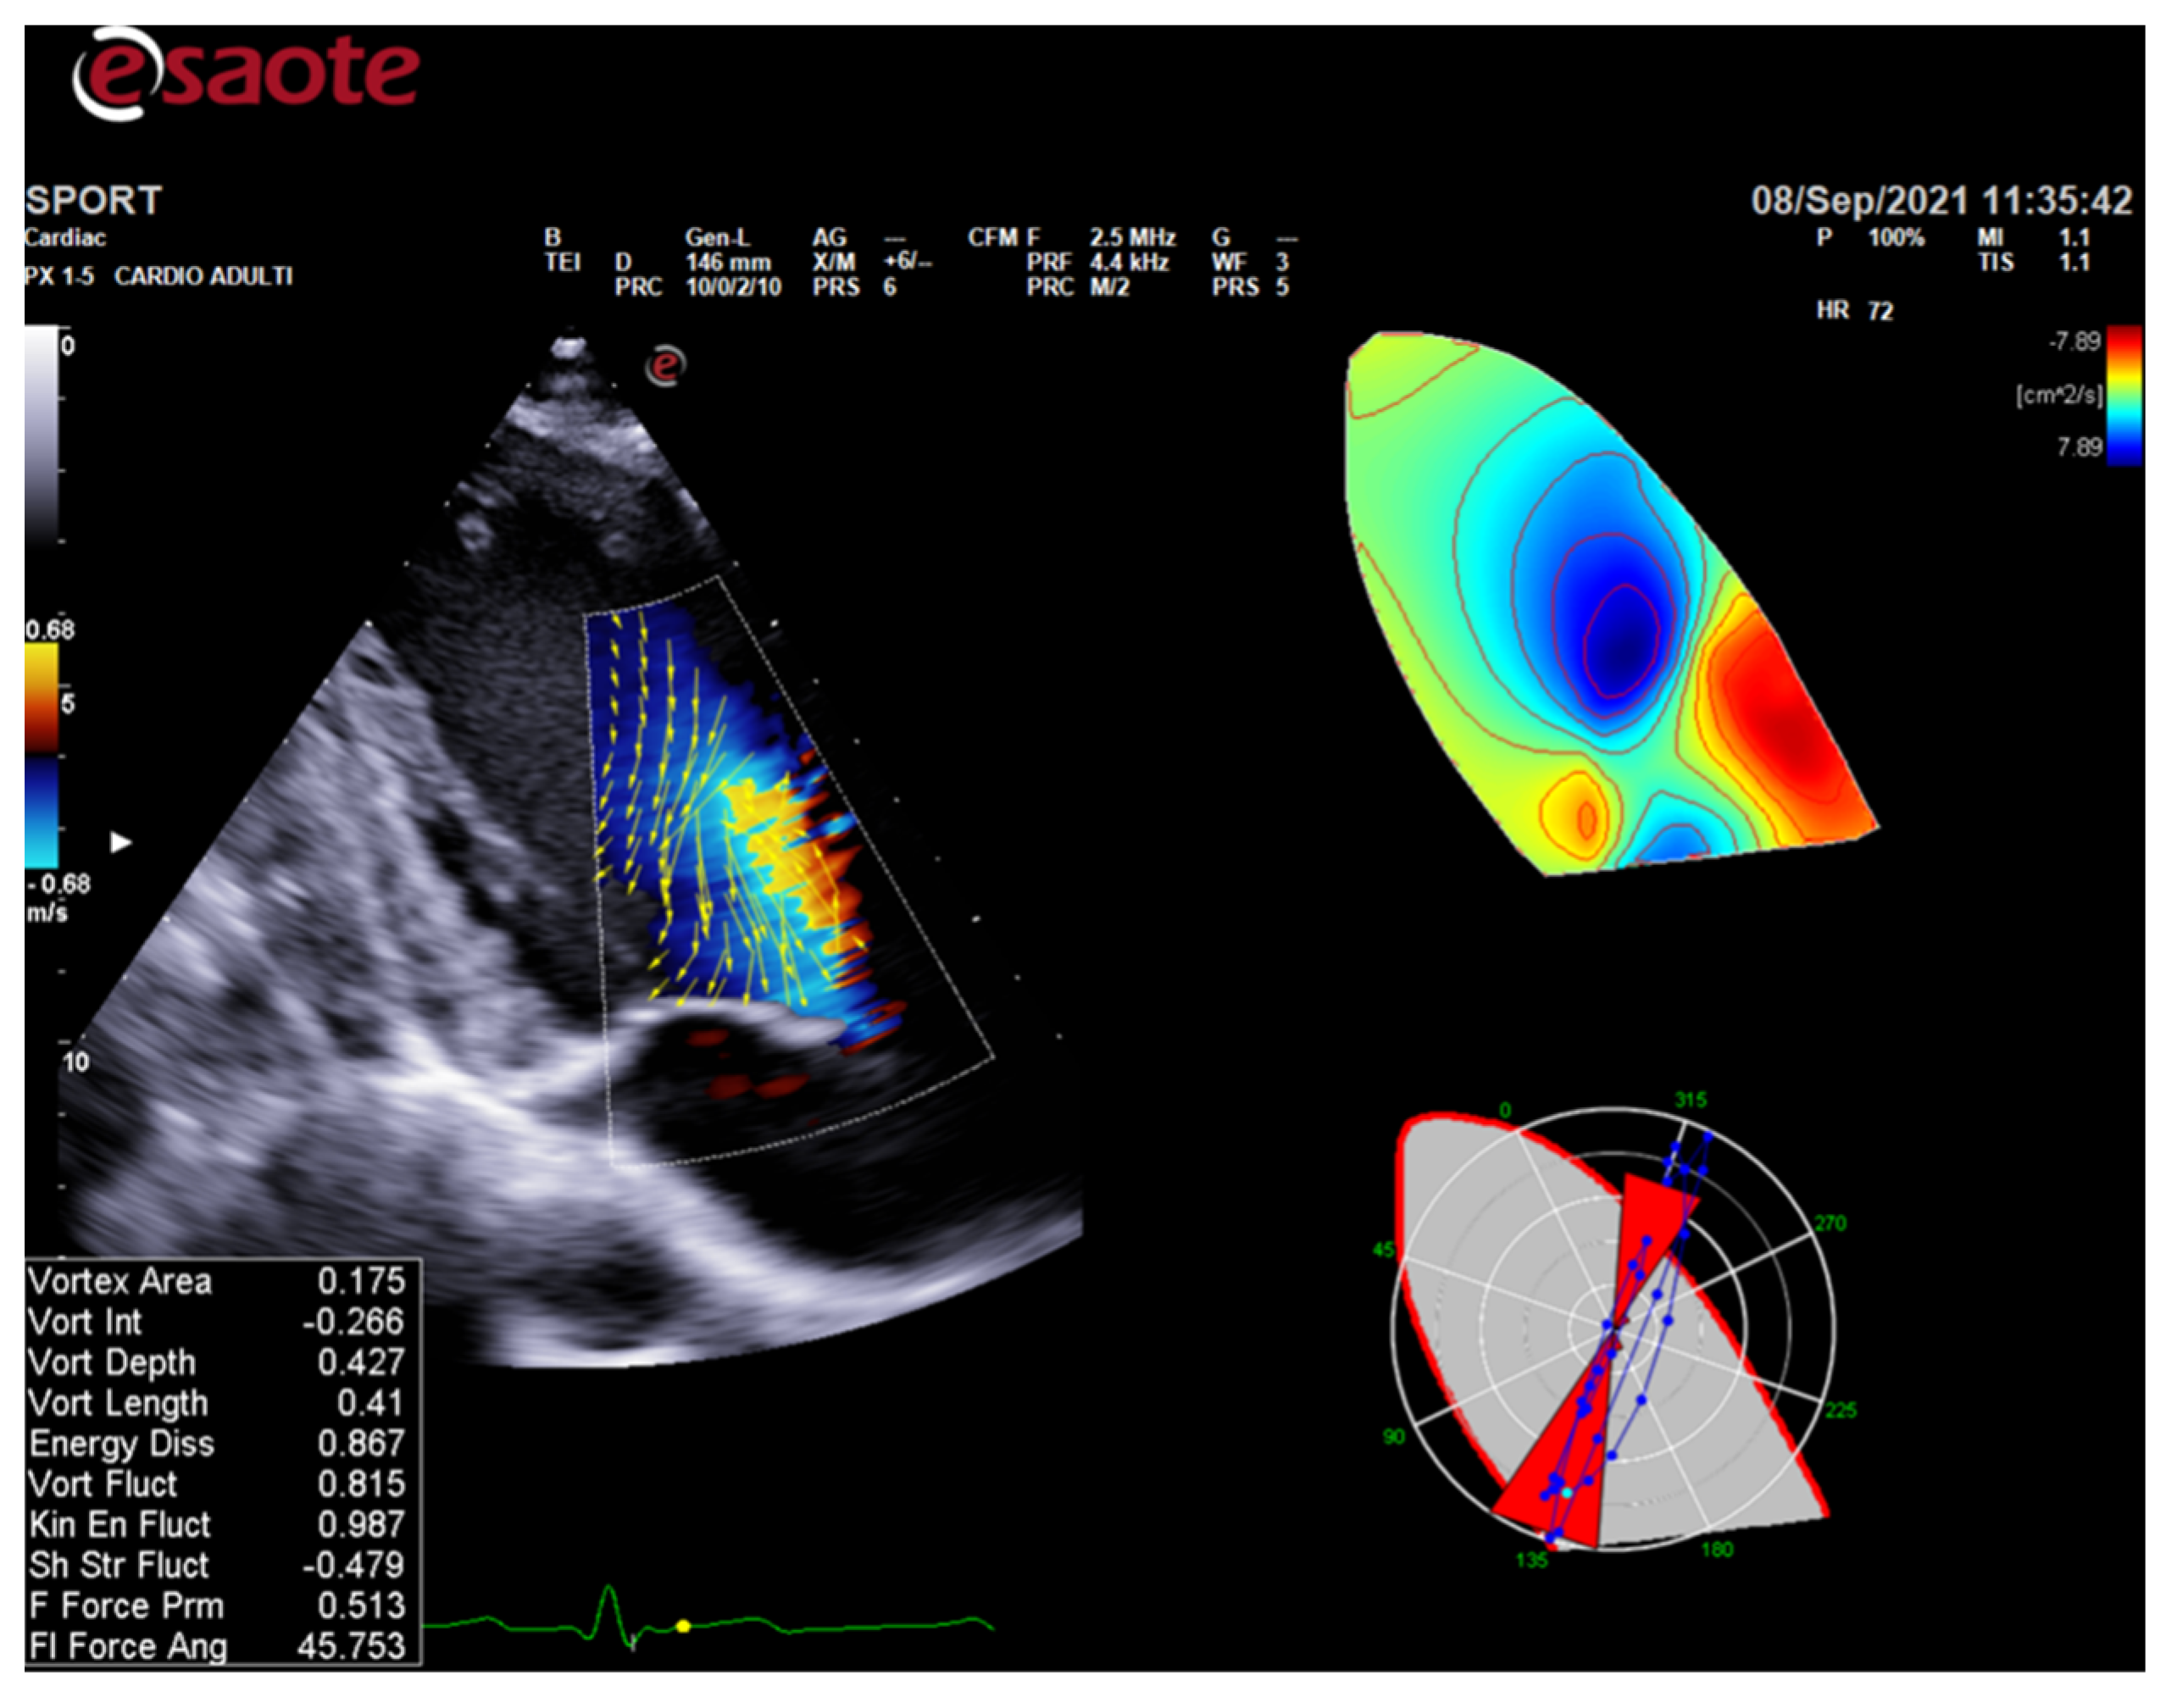

ColorDoppler flow mapping is an advanced echocardiographic tool that evaluates LV function through the analysis of intracardiac flows [56]. LV vortex flow study may provide new insights into the characterization of athlete’s heart properties and its differences with normal subjects and patients with cardiomyopathies (Figure 3).

Figure 3.

HyperDoppler flow analysis in an endurance athlete. On the left, the flow velocity vector map shows the blood flow that circulates towards the direction of the left ventricular outflow tract. On the right, the circulation parametric map brings to light the formation of a pair of vortices immediately below the aortic valve.